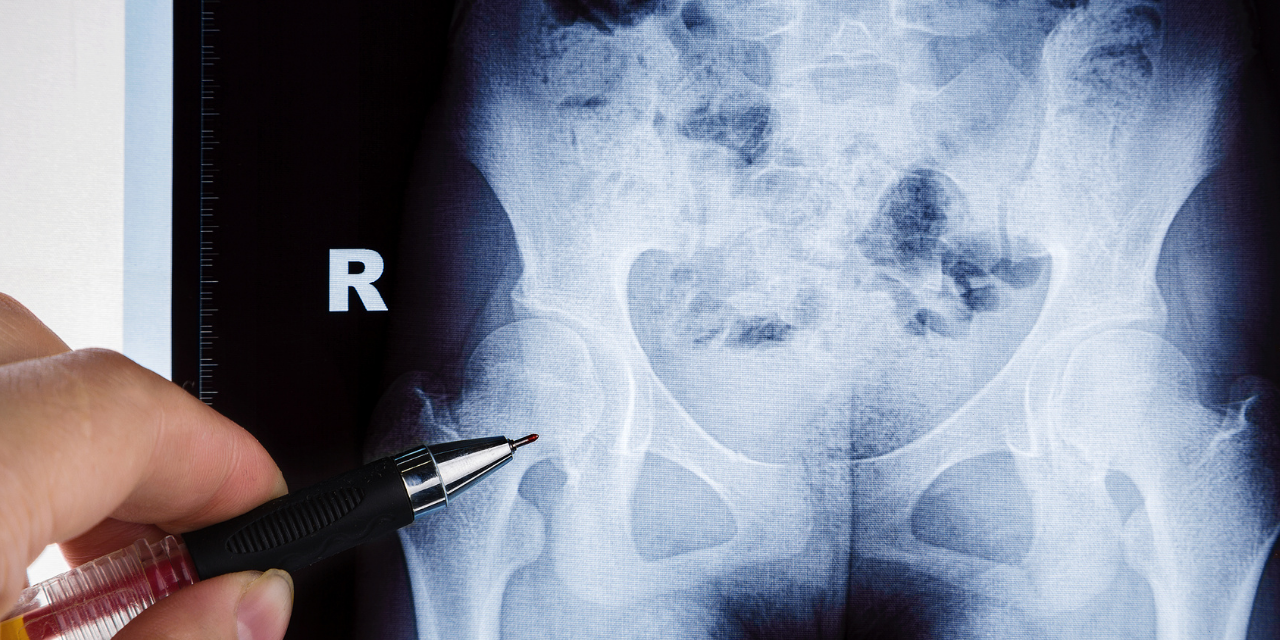

Depending on the site of involvement, the radiographic appearance of osteonecrosis can vary. When involving the femoral epiphysis, for example, there may be femoral head collapse, a fragmented appearance to the head, disruption of the trabecular pattern, increased density of the head, the formation of subchondral cysts and eventual subchondral fracture.

Images 1, 2 and 3 demonstrate various appearances in the hip. Figure 1 features a degree of articular collapse of the right femoral head. In figure 2 there is a mottled appearance of the left femoral head without obvious articular collapse. Figure 3 combines a dense mottled appearance of the head with obvious articular collapse. A similar appearance is noted in the right shoulder (Figure 4).